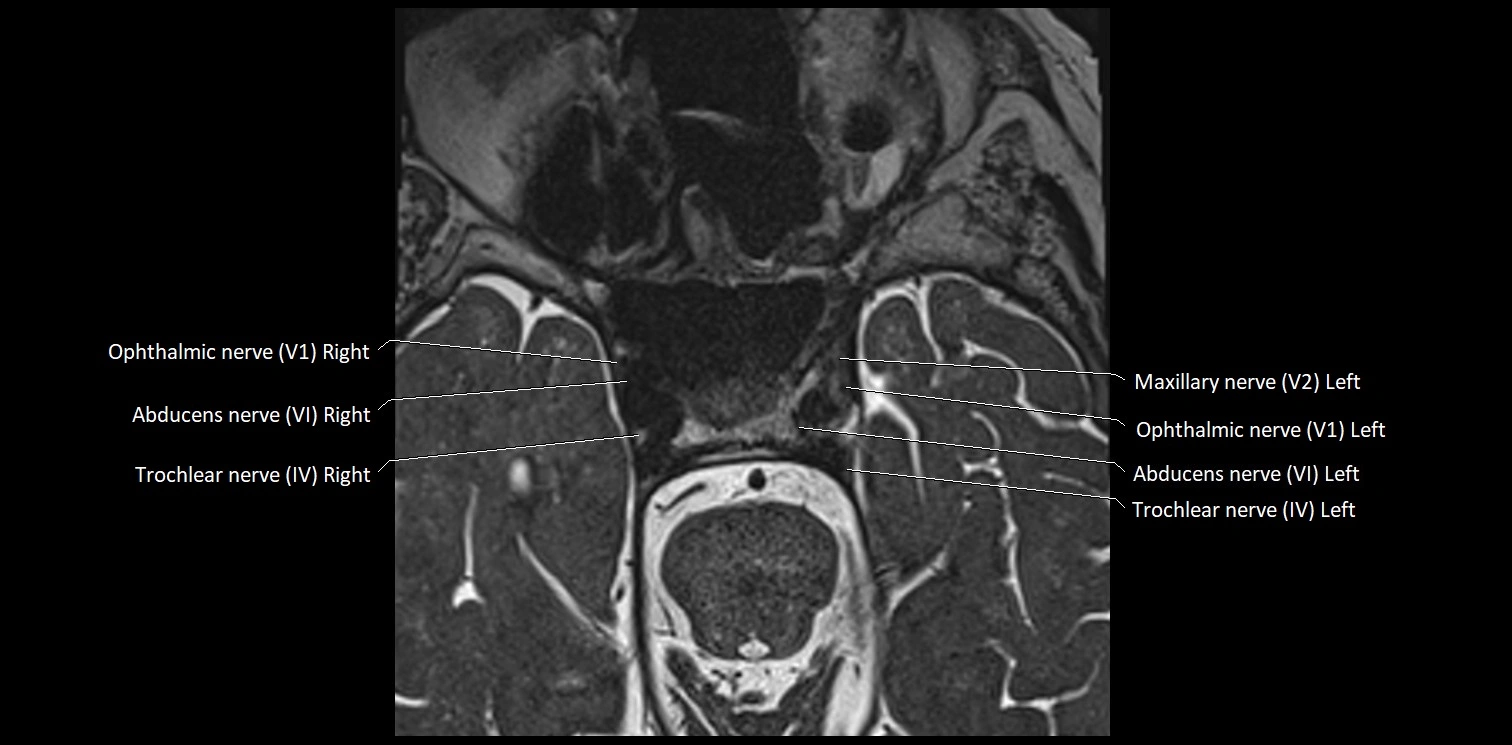

• The abducens nerve is a small, thin, linear structure

• Best visualized on high-resolution T2-weighted 3D MRI sequences (e.g., FIESTA or CISS)

• Seen as a hypointense (dark) line running from the brainstem at the pontomedullary junction, traversing the prepontine cistern, and entering Dorello’s canal under the petrosphenoidal ligament, then into the cavernous sinus, and finally the orbit

• May be challenging to visualize in standard MRI due to its small size

• Pathology may be inferred by absence, displacement, or enhancement of the nerve